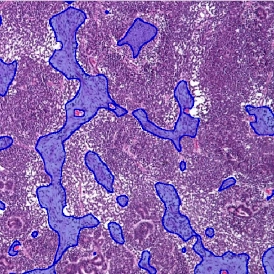

The IHC Tumor-Stroma App combines the segmentation of tumor and stroma (based on the morphology) and the detection of specifically stained cell populations. It segments the cells into their nucleus, perinuclear area, and/or cytoplasm. Each segmented cell compartment in tumor and/or stroma is measured for up to 20 intensity, statistic, and morphometric parameters that can be displayed in and exported into scattergrams and histograms.

App Category 2